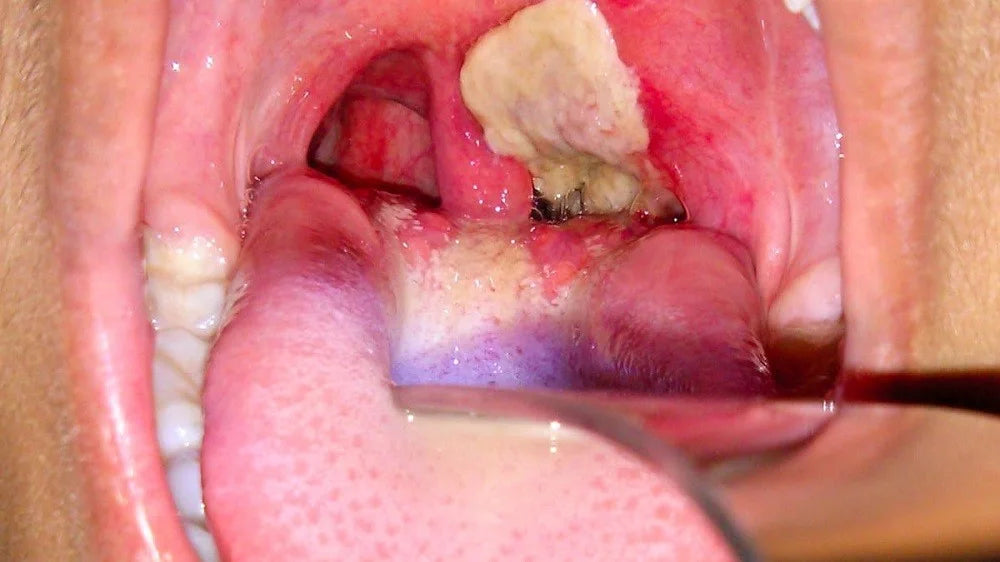

Las sintomatología se pueden presentar entre 2 a 10 días después del contagio. En algunas ocasiones es posible que las afecciones se noten en la piel al producirse ulceraciones y cambio de tonalidad. Sin embargo, ataca normalmente a través de las vías respiratorias. Por lo general, se puede ver una membrana de color gris o negro en la garganta, la cual es fibrosa y generará graves problemas respiratorios. A pesar de esto, es necesario tomar en cuenta los otros síntomas que son los más frecuentes: